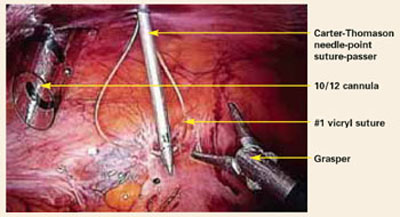

In addition to closing the peritoneum and fascia at all sites greater than 5 mm, you can prevent trocar site hernias by avoiding extensive manipulation, carbon dioxide leakage during the course of surgery, and repeated replacement of the cannula, all of which can contribute to trocar site dilatation.

Trocar sites may be associated not only with hernias—which cause acute and severe symptoms requiring immediate intervention—but also with adhesions resulting in chronic pelvic pain.

When patients postoperatively complain of pain, nausea, and vomiting, and a mass is palpable at the trocar site, a port site hernia should be suspected. Plain abdominal x-rays usually indicate a partial small bowel obstruction. In such cases, promptly obtain a computed tomography (CT) scan, which will confirm the diagnosis. This condition can be managed laparoscopically if it is diagnosed early, but the operator must take extra care when making the initial abdominal entry.